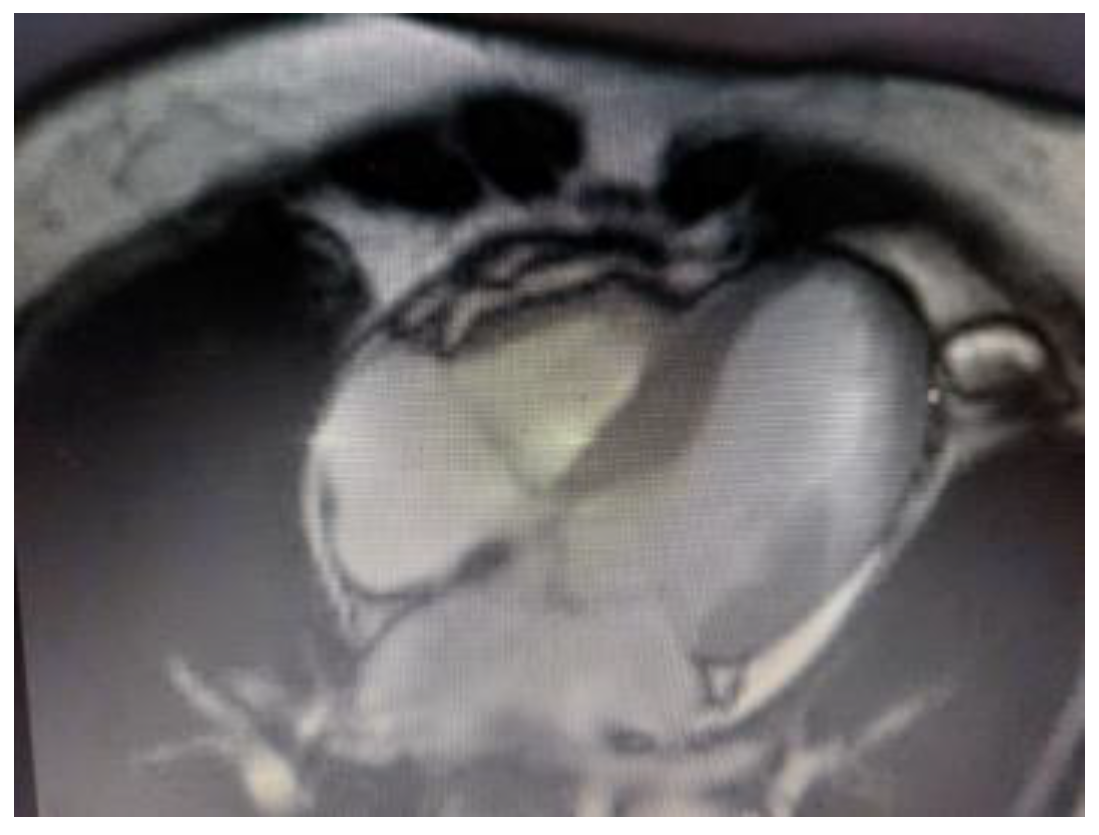

10.5. Cardiac Magnetic Resonance